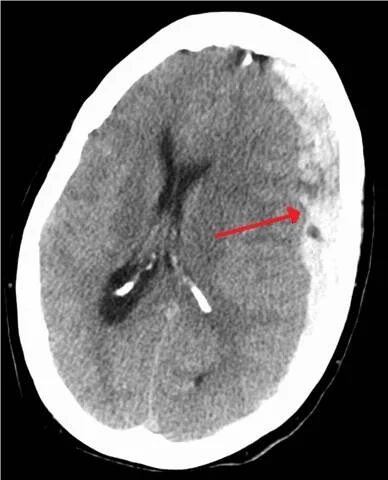

Brain scans may reveal a subdural hematoma and even a shift of the brain beyond the midline and ventricles. This is called a midline shift.

See image:

Image source: https://commons.wikimedia.org/w/index.php?curid=19364350

picture with subdural hematoma By James Heilman, MD - Own work, CC BY-SA 3.0, https://commons.wikimedia.org/w/index.php?curid=19364350